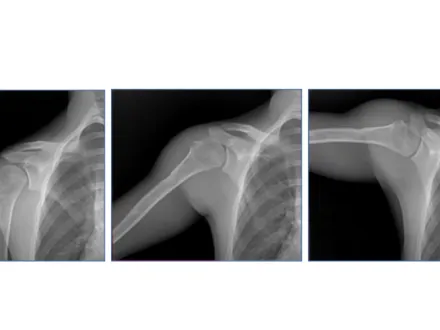

Wayne, NJ, March 2, 2026 – Konica Minolta Healthcare Americas, Inc. congratulates Emory Healthcare researchers, led by Dr. Eric R. Wagner, on their recently published study comparing two well-established treatment options for cuff-intact glenohumeral osteoarthritis in the shoulder. Using Dynamic Digital Radiography (DDR), the team evaluated which surgical technique most effectively restores native shoulder biomechanics. The alterations in scapular motion and their clinical significance in patients with glenohumeral osteoarthritis following total shoulder arthroplasty is poorly understood. Using DDR to non-invasively image the shoulder while in motion, the researchers aimed to quantify the scapular contributions to shoulder elevation in patients after anatomic total shoulder arthroplasty (aTSA) and reverse total shoulder arthroplasty (rTSA). The study is available in the Journal of Shoulder and Elbow Surgery.

While it is well known that after undergoing shoulder arthroplasty, patients have a reduced scapulohumeral rhythm (SHR) compared to healthy subjects, it remains unclear whether the lower SHR is related to preoperative pathology or surgical intervention. Deciding between the aTSA and rTSA techniques may be difficult in younger, more active patients. In a retrospective analysis of 71 shoulders treated with either arthroplasty technique compared to 32 normal controls, the authors report similar SHR for aTSA and rTSA, although neither achieved physiologic biomechanics. They also found that while the rTSA cohort had a fairly constant SHR throughout shoulder elevation, aTSAs had a higher SHR in the second half of shoulder motion compared to the first half, suggesting higher glenohumeral involvement as abduction progresses.

DDR is a novel, low-dose X-ray imaging technique available from Konica Minolta Healthcare that captures as series of static images acquired in quick succession, known as a cinegrams, providing an innovative way to obtain detailed images of complex joints like shoulders while in motion. By acquiring a series of images at high speed, DDR generates a cineloop that enables clinicians to visualize anatomical motion over time (cineradiography), enhancing the system’s diagnostic capabilities. Konica Minolta Healthcare will showcase DDR during the American Academy of Orthopedic Surgeons (AAOS) 2026 Annual Meeting, being held March 2-6, 2026, in New Orleans, in booth 2813.